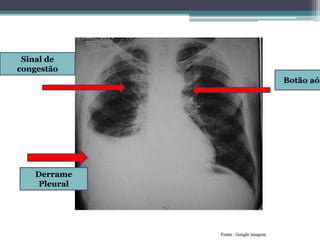

Derrame

Pleural

Sinal de

congestão

Botão aór

Fonte : Google imagem